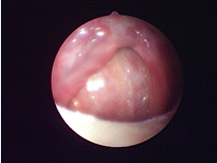

適于精確損毀破壞內部組織。

適合于精準的點狀凝血。

適合于在重要的部位實現凝血。